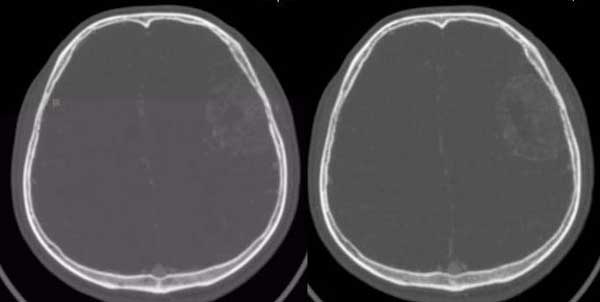

左颞部稍低密度d形肿块影阴,密度不均,内有不规则囊变区,局部脑白质受压塌陷,肿块周围少许水肿带,中线轻度右移位,增强扫描明显强化,局部颅板有轻微侵蚀,如此大的肿块中线结构移位不明显说明肿块位于脑外,如此强化的脑外肿瘤只有一个------脑膜瘤

与颅骨广基相连,不均匀强化,脑白质受压,考虑脑外肿瘤,脑膜瘤。

皮质塌陷,增强比较明显,有一定的占位效应,脑内水肿不显著,脑外病变可肯定,考虑脑膜瘤,但平扫密度较低,颅骨改变也不明显,确实应排除一下脑血管病.

皮质塌陷,增强比较明显,有一定的占位效应,脑内轻度水肿,脑外病变可肯定,考虑脑膜瘤,颅骨内板见局限侵袭改变,警惕恶变

支持脑膜瘤的地方:强化明显,水肿轻,中线移位不明显(但颅顶层面有大脑镰限制也不好说),相应脑灰质受压内移。